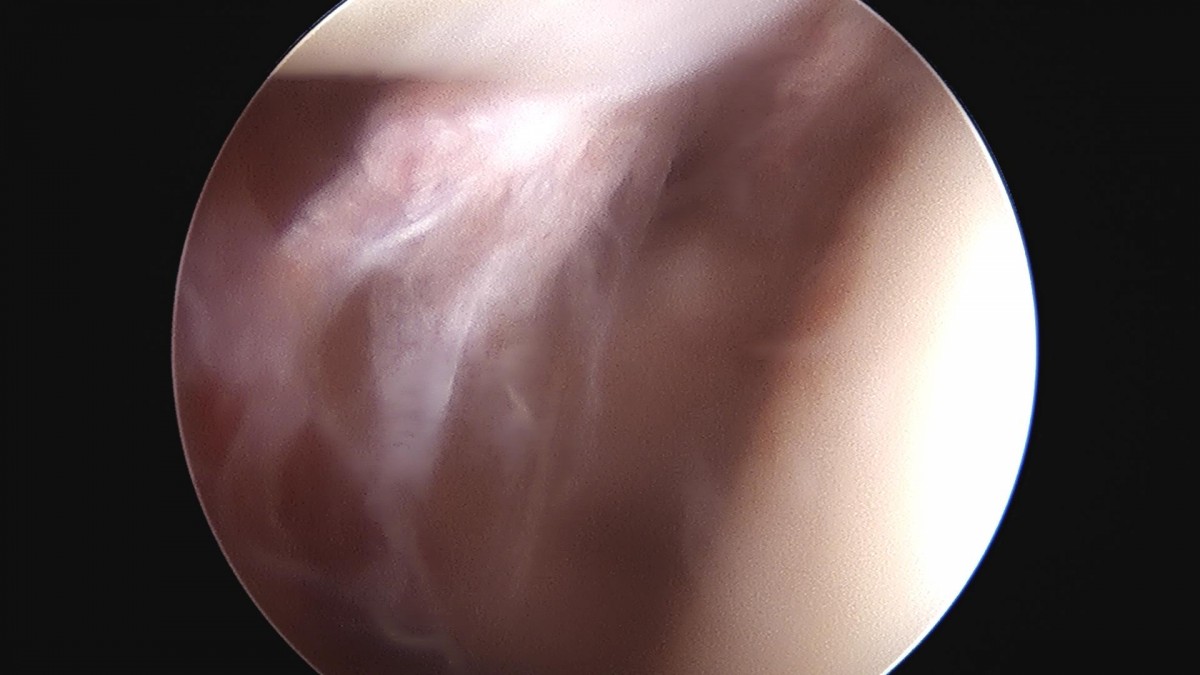

이재상원장님 어깨 회전근개 봉합술 김순O 환자

작성자 최고관리자 댓글 0건 조회 1,690회 작성일 24-10-16 16:23